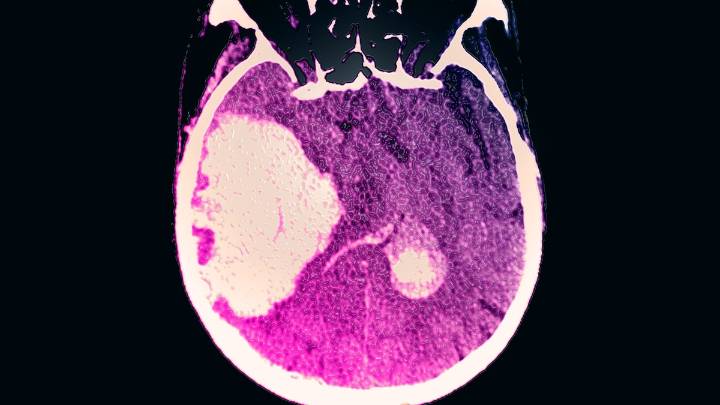

It’s long been known that heavy drinking raises blood pressure and damages the liver . But new research suggests it may also deal a devastating blow to the brain—causing life-threatening hemorrhagic strokes.

The study , published November 5 in Neurology, found that people who consumed three or more alcoholic drinks a day experienced bleeding strokes inside the brain an average of 11 years earlier than light or non-drinkers—and faced worse outcomes such as larger bleeds, greater brain damage, and higher mortality.

“Heavy alcohol use may not only increase the risk of having a brain bleed at a younger age, but may also worsen the underlying damage when one occurs,” says Edip Gurol , lead author of the study and